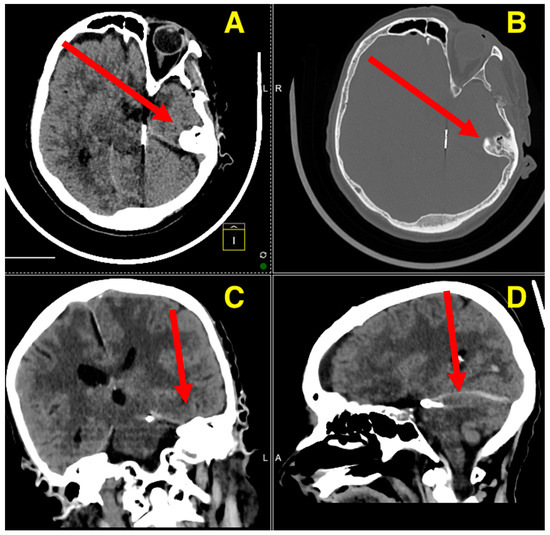

Preoperative cerebral angiography (Figure 1) confirmed the presence of a saccular aneurysm located on the SCA. The aneurysm was clearly visualized in the angiographic series, with lateral, oblique, and anterior–posterior views revealing its close proximity to the basilar artery bifurcation and the posterior cerebral arteries (PCAs). The SCA, a critical vessel supplying the cerebellum and brainstem, places the aneurysm in a high-risk location, with potential involvement of the oculomotor nerve (CN III), given its anatomical course. This could explain the patient’s neurological presentation, including moderate somnolence and meningeal irritation, while also raising the risk of further complications such as brainstem compression or cranial nerve deficits. The aneurysm’s location, in proximity to the pons and midbrain, also poses the threat of cerebellar dysfunction and further neurological deterioration, aligning with the acute onset of severe headache, nausea, and vomiting. The angiographic findings supported the initial clinical concern for a subarachnoid hemorrhage, underscoring the need for urgent neurosurgical intervention.

Figure 1. The preoperative angiography demonstrates a ruptured aneurysm located on the middle portion of the left SCA, oriented laterally and posteriorly, with a neck measuring approximately 2 mm in diameter. The maximal dimensions of the aneurysmal sac are approximately 4.7 mm in length and 3.4 mm in width. The vascular imaging outlines the aneurysm’s proximity to the basilar artery bifurcation and its relationship to the surrounding posterior circulation vessels. The lateral projection (A) highlights the aneurysm’s orientation and size relative to the parent vessel, emphasizing its lateral and posterior direction, with no apparent filling defects or thrombus within the aneurysmal sac. The anteroposterior view (B) delineates the aneurysm’s position along the superior cerebellar artery and its anatomical relationships with the basilar artery and posterior cerebral arteries, clearly defining the vascular bifurcation anatomy and aiding in surgical planning. The oblique projection (C) provides additional depth perception of the aneurysm’s spatial orientation, confirming its posterior and lateral projection from the SCA, and offers a detailed understanding of the aneurysm’s dome-to-neck ratio, which is crucial for selecting the surgical approach. The rotational view (D) emphasizes the three-dimensional architecture of the aneurysm, providing comprehensive insights into its morphology and the involvement of adjacent vascular structures. These angiographic findings underscore the complexity of the aneurysm’s location, necessitating meticulous planning for surgical clipping. The precise measurements and detailed visualization provided by the angiography were instrumental in guiding the decision to proceed with a left-sided occipito-parietal far-lateral approach, ensuring optimal exposure and minimizing risks to critical neurovascular structures.